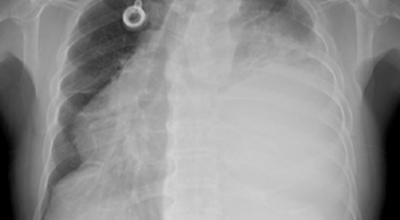

폐암 검사는 X-ray를 통해서 검사하는데 , 크기가 작거나 구석에 위치한 경우 확인이 어려운 경우도 있답니다. 그리고 조직 검사를 통해서 정확한 진단을 하게 돼요. 폐암이 발견되면 종양의 크기나 전이 여부 , 위치에 따라서 수술 여부를 결정하게 돼요.